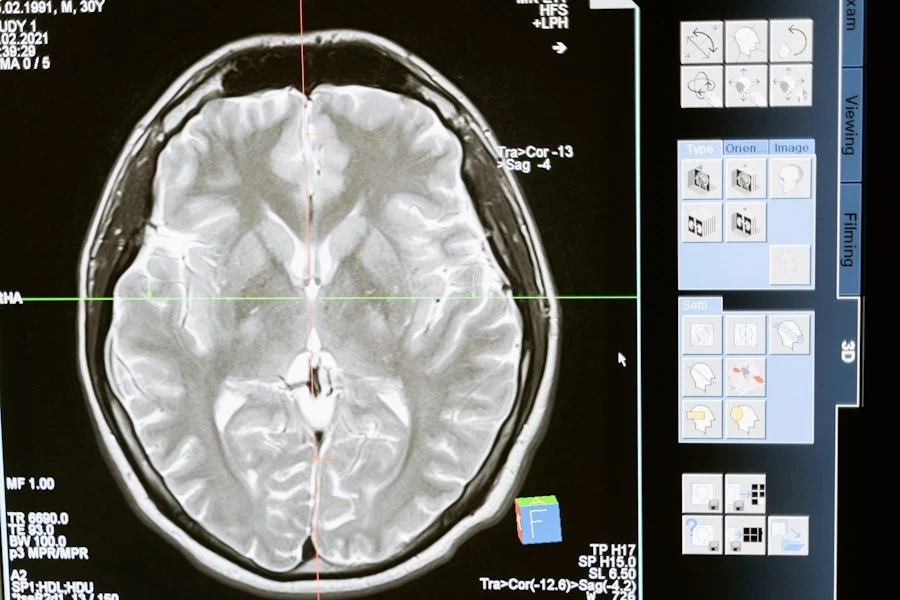

Ученые из University of Texas at Austin разработали инновационные текучие чернила для электроэнцефалографии (ЭЭГ). Этот метод исследования активности мозга стал не только точнее, но и комфортнее для пациентов.

Сейчас стандартный процесс ЭЭГ требует прикрепления десятков электродов к коже головы. Это не только занимает много времени, но и вызывает дискомфорт, особенно при длительных исследованиях. Новая технология решает эти проблемы с помощью электронных татуировок (e-tattoos).